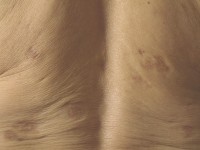

Amyloidosis cutis maculosa (macular or interscapular cutaneous amyloidosis) wordt klinisch gekenmerkt door een onscherp begrensde gehyperpigmenteerde jeukende huid, soms met krabeffecten, lichenificatie, lichen simplex chronicus-achtig beeld. Komt vaker voor bij mensen uit Azië, Zuid-Amerika, Midden-Oosten. De oorzaak is onbekend; mogelijk zijn maculaire amyloidosis en lichen amyloidosis uitingen van dezelfde aandoening en speelt jeuk een rol. Maar de jeuk kan bij maculaire amyloidosis mild zijn of afwezig, en de huid vertoont meestal geen lichenificatie of andere krabeffecten. Er bestaan familiaire vormen van primaire cutane amyloidosis waarbij een mutatie in een receptor voor IL31 en oncostatin M is gevonden. Kan overal op lichaam voorkomen, vaak op rug en schouders. Ook op de armen en de benen. Soms plaatselijk toch ook wat papuleus. Typisch is de aanwezigheid van lineaire gehyperpigmenteerde lijnen in een golfjespatroon (rippled hyperpigmentation), vooral te zien bij een (licht) gepigmenteerde huid. Amyloidosis cutis is moeilijk te behandelen. Het bestrijden van droge huid en jeuk kan helpen. De hyperpigmentatie is moeilijk te behandelen. In case reports wordt effect van pulsed dye laser en Q-switched Nd:YAG laser beschreven, maar de afwijkingen zijn meestal te uitgebreid om dat te gaan proberen. In systematische reviews naar de behandeling van cutane amyloidosis is de conclusie dat de evidence ontbreekt om aanbevelingen te doen.

amyloidosis cutis maculosa amyloidosis cutis maculosa golfjes patroon